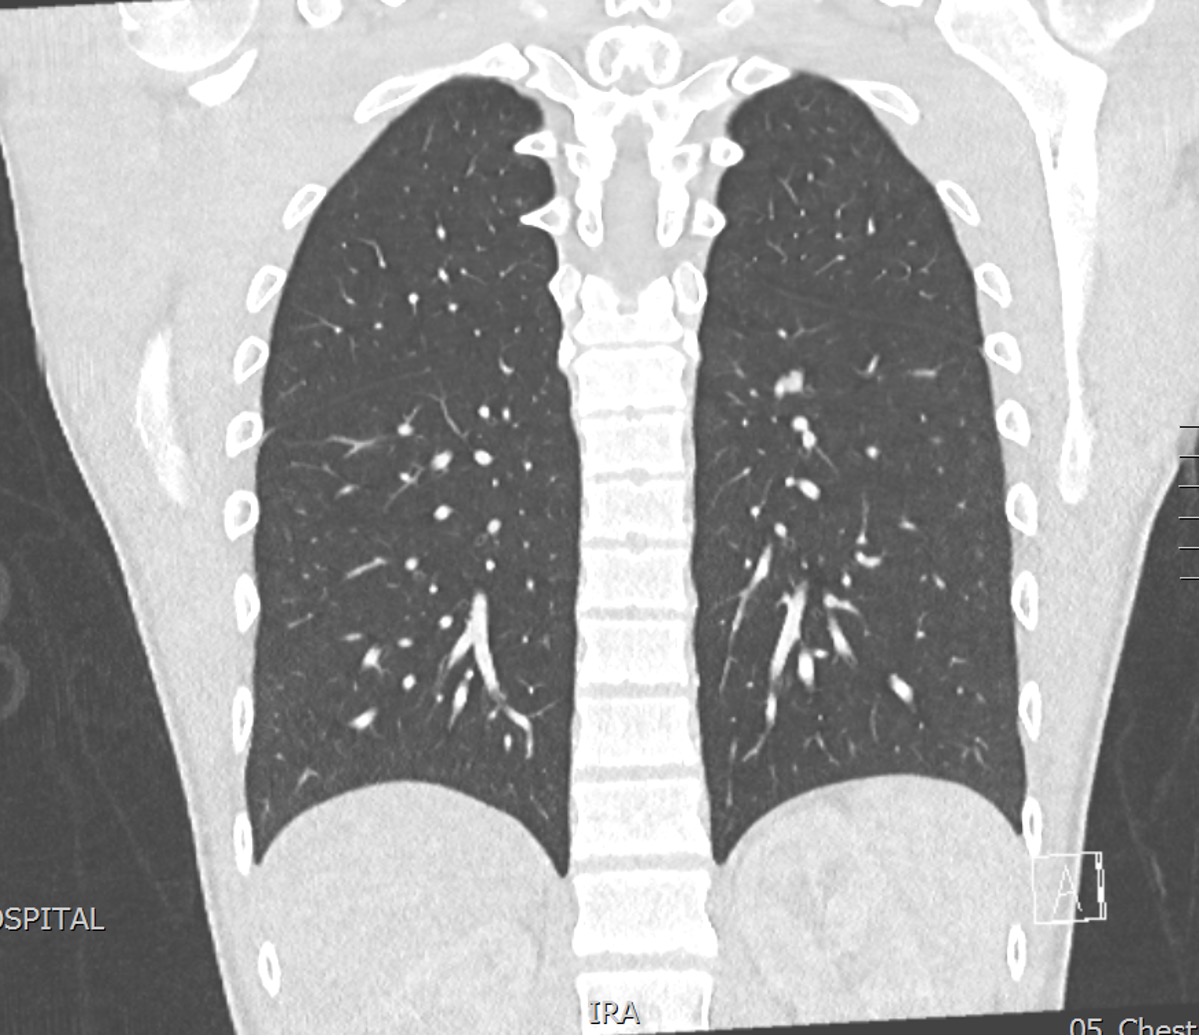

CT Chest / abdomen

Pulmonary metastasis

Metastasis

Mettman et al, Cancer Med 2023

- Retrospective RV of 219 osteosarcoma patients who relapsed with a single pulmonary nodule

- 94.9% achieved successful resection of nodule

- 5y survival post complete resection was 51%, compared to 0% if incomplete